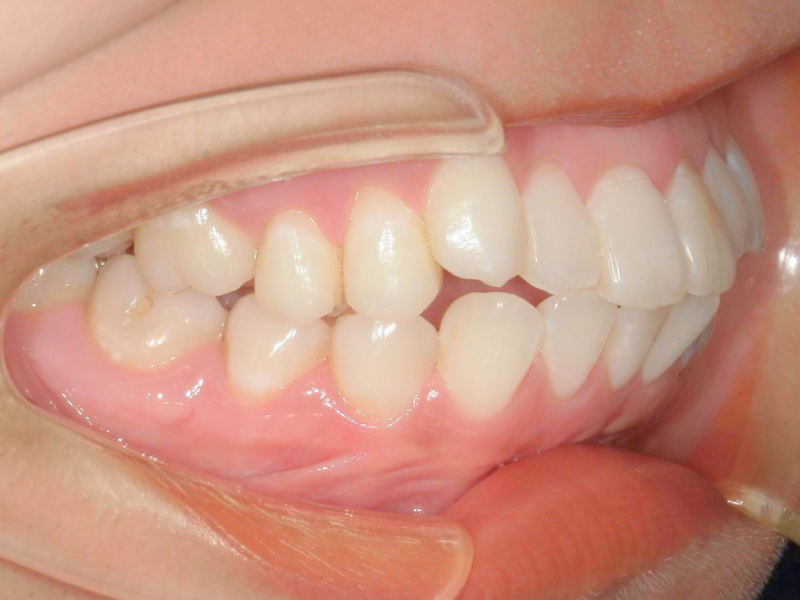

40代、女性、マウスピース

| 施術内容 | 主訴:噛み合わせが深い、前歯が出てるのが気になる 詳細:マウスピース矯正を装着しての歯並び改善 |

|---|---|

| 治療期間 | 20ヶ月(7/11現在 治療終了) |

| リスク・副作用 | ・治療の初期段階では、痛みや不快感が生じやすくなりますが、一週間前後で慣れます。 ・歯の動き方には個人差があるため、予想された治療期間より延長する場合があります。 |

| 費用 | 枚数無制限 48万(税込528,000円) |